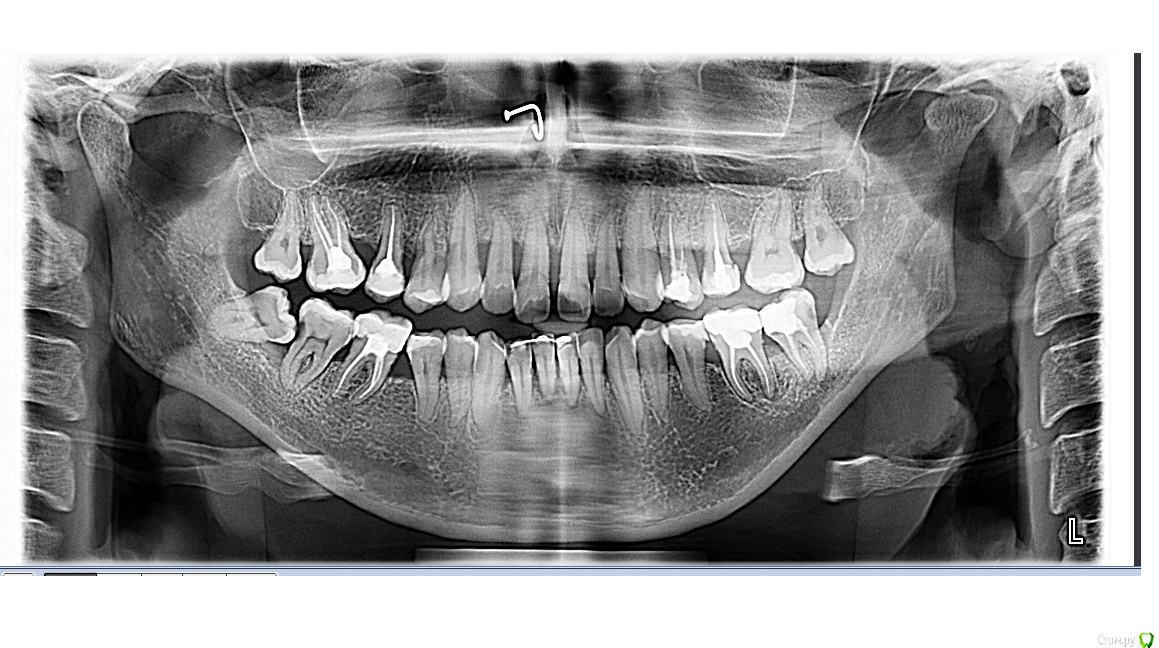

Chudo Опубликовано 14 октября, 2017 Поделиться Опубликовано 14 октября, 2017 Здравствуйте. Нужна консультация. Мне 30 лет, у меня остеопороз. 3 года после родов хожу лечить зубы как на работу (после родов состояние зубов плачевное, на панорамном снимке все видно). Сначала просто лечили кариес, удаляли нервы, ставили пломбы. У меня было две нижних 8 которые сильно сдавили мне все зубы. Мой врач все время говорила что надо ставить брекеты из-за неправильного прикуса, но денег и времени не было (маленький ребенок, отец инвалид 1 группы и муж в бесконечных командировках). В конце 2015 года я пошла удалять восьмерку, так как боль от давления на зубы стала нестерпимая. Располосовали щеку что бы поддеть 8 которая стояла горизонтально(снимок перед удалением 8 прилагаю). Зуб удаляли в Краевом клиническом стоматологическом центре Гбуз г. Краснодар. Заживало долго потому как в щеке остался осколок челюсти, месяц я ходила на перевязку и жаловалась на боль в щеке и на застрявшие нити от бинта который мне запихивали в лунку в десне, нити я вытаскивала дома сама потому что врачи их не видели, а я почему то да (никакой реакции со стороны врача не было. Я слышала только : это нормально, все пройдет). Через месяц у меня начала подниматься температура, а потом осколок из щеки стал выходить вместе с гноем из того места где мне резали щеку при удалении 8. В итоге спустя два месяца после этого удаления начался кошмар. У меня пошло воспаление по всей полости рта и верхние передние зубы начали расходиться. Все это время ходила лечила десны. Прижигала лазером воспаления в деснах, полоскала, мазала гелями, врачи все говорила что у меня просто организм подвержен постоянному воспалительному процессу и уммунитет у меня никакой . В начале 2017 дочка ударила меня затылком по нижним передним зубам, из-за чего 1 зубы стал шататься и на приему у своего зубного выяснилось, что у меня пародонтоз и что зуб у меня держится на одной только десне. Сделала мне шинирование шатающегося зуба с рекомендацией мазать гелем метрогил дента что бы десна пришла в себя и через месяц придти на прием и снять шинирование. Через месяц ситуация не улучшилась, шинирование оставили, продолжала ходить через 1-2 месяца на чистку зубов от камня и налета.В общем какая сейчас ситуация. В начале этого лета мне сказали что без брекетов я потеряю зубы, после нового снимка ортодонт сказала что брекеты она мне ставить не может из-за пародонтоза чуть ли не 3 степени и ужасного состояния моей челюсти и что зубы у меня выпадут из-за этого еще быстрее. Импланты мне сказали ставить просто некуда из-за малого количества челюстной кости. После 2 месяцев соображений ортодонт выдвинули вердикт ставить мне брекеты на мой страх и риск, если зубы выпадут, будут делать какие то протезы которые будут крепиться к боковым зубам. Ответа внятного почему мне за все это время не предлагали адекватного лечения пародонтоза я не услышала, теперь есть то, что есть ...Вот у меня к Вам дорогие специалисты 2 вопроса 1. Какова вероятность выпадения зубов при брекетах в моем случае? Я знаю что обязательно нужно вычистить все пародонтальные карманы, снять воспаление и т.д. То есть меня интересует можно ли вообще теоретически поставить брекеты с такой ушатаной челюстной костью?2. И если брекеты ставить нельзя, то что вообще делать? P.S.: Еще лет в 17 - 18 было удалено по 5 с верхней челюсти с обеих сторон из-за воспаления надкостницы (удаляли не за раз, а с интервалом в год). Рентген снимка с боку не было, есть снимок МРТ, может быть хоть чуть чуть будет что-то на них видно Ссылка на комментарий

___49___ Опубликовано 17 октября, 2017 Поделиться Опубликовано 17 октября, 2017 На снимке до удаления 8ки явления пародонтита уже есть . Брекеты ставить смысла не вижу, шинировать - да . Вашим основным лечащим должен быть пародонтолог. Именно он может помочь получить стойкую ремиссию, так же необходимо определить факторы усугубляющие течение заболевания( диабет, системные заболевания, прием лекарственных средств, гормональный статус и т.д.) 1 Ссылка на комментарий